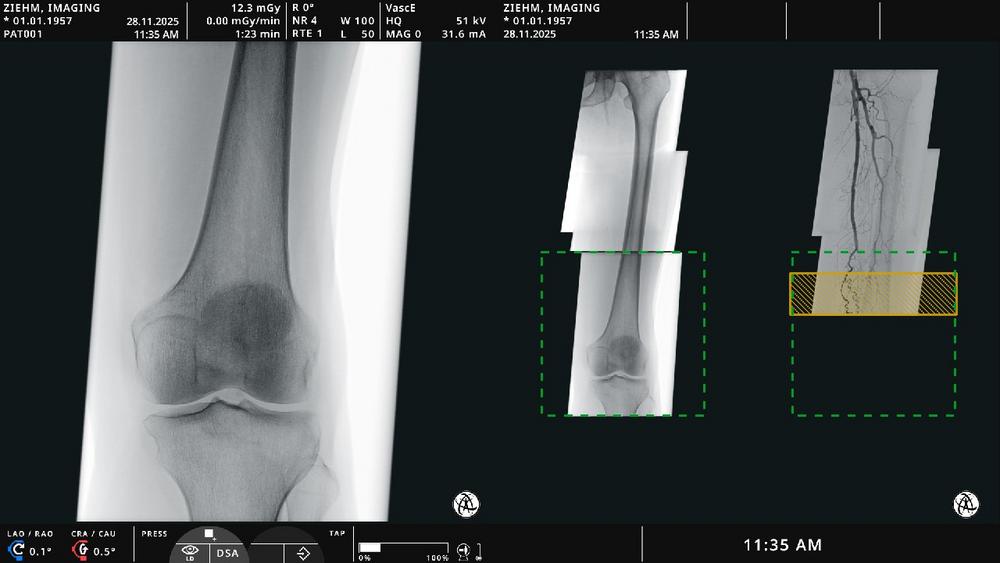

Endovascular Navigation Peripheral allows for panorama creation for peripheral artery disease cases by stitching fluoroscopic and angiographic images into a complete, up-to-date overview. Thrombotic and stenotic areas can be easily identified and marked. “Live fluoroscopic images align precisely with the angiographic panorama through image fusion—allowing clinicians to navigate with ease and optimal orientation without additional contrast media,” says Martin Törnvik, Vice President Global Sales & Marketing. Artificial intelligence-based algorithms automatically match and display image fusion – adapting in real time to patient, table, or C-arm movement. The solution is fully integrated into Ziehm Vision RFD Hybrid Edition3 (Cardio) and Ziehm Vision RFD 3D.